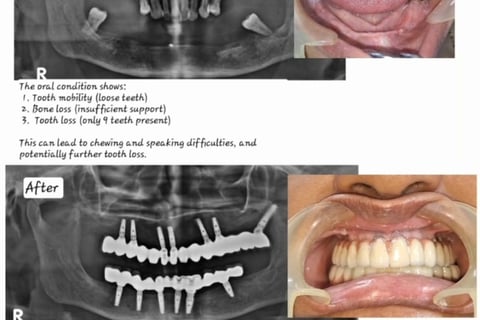

Full mouth implant cases in affordable treatment option

FIX TEETH WITH DENTAL IMPLANTS

Revolutionize Your Smile with Dental Implant